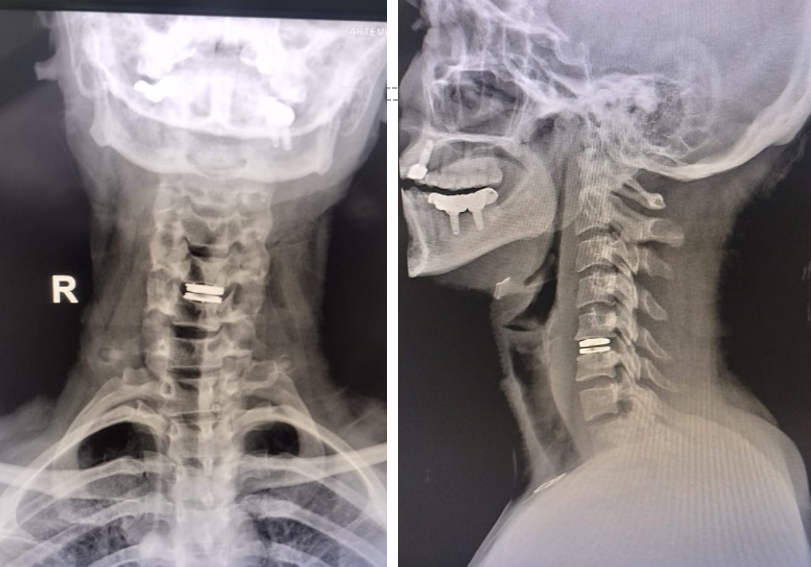

What is Artificial Disc Replacement?

A surgery where a damaged spinal disc is removed and replaced with an artificial one that allows normal spine movement.

How is it Performed?

Disc Removal

Through a small incision in the neck or abdomen, the damaged disc is removed.

Artificial Disc Placement

The damaged disc is replaced with an artificial disc to maintain spine movement.